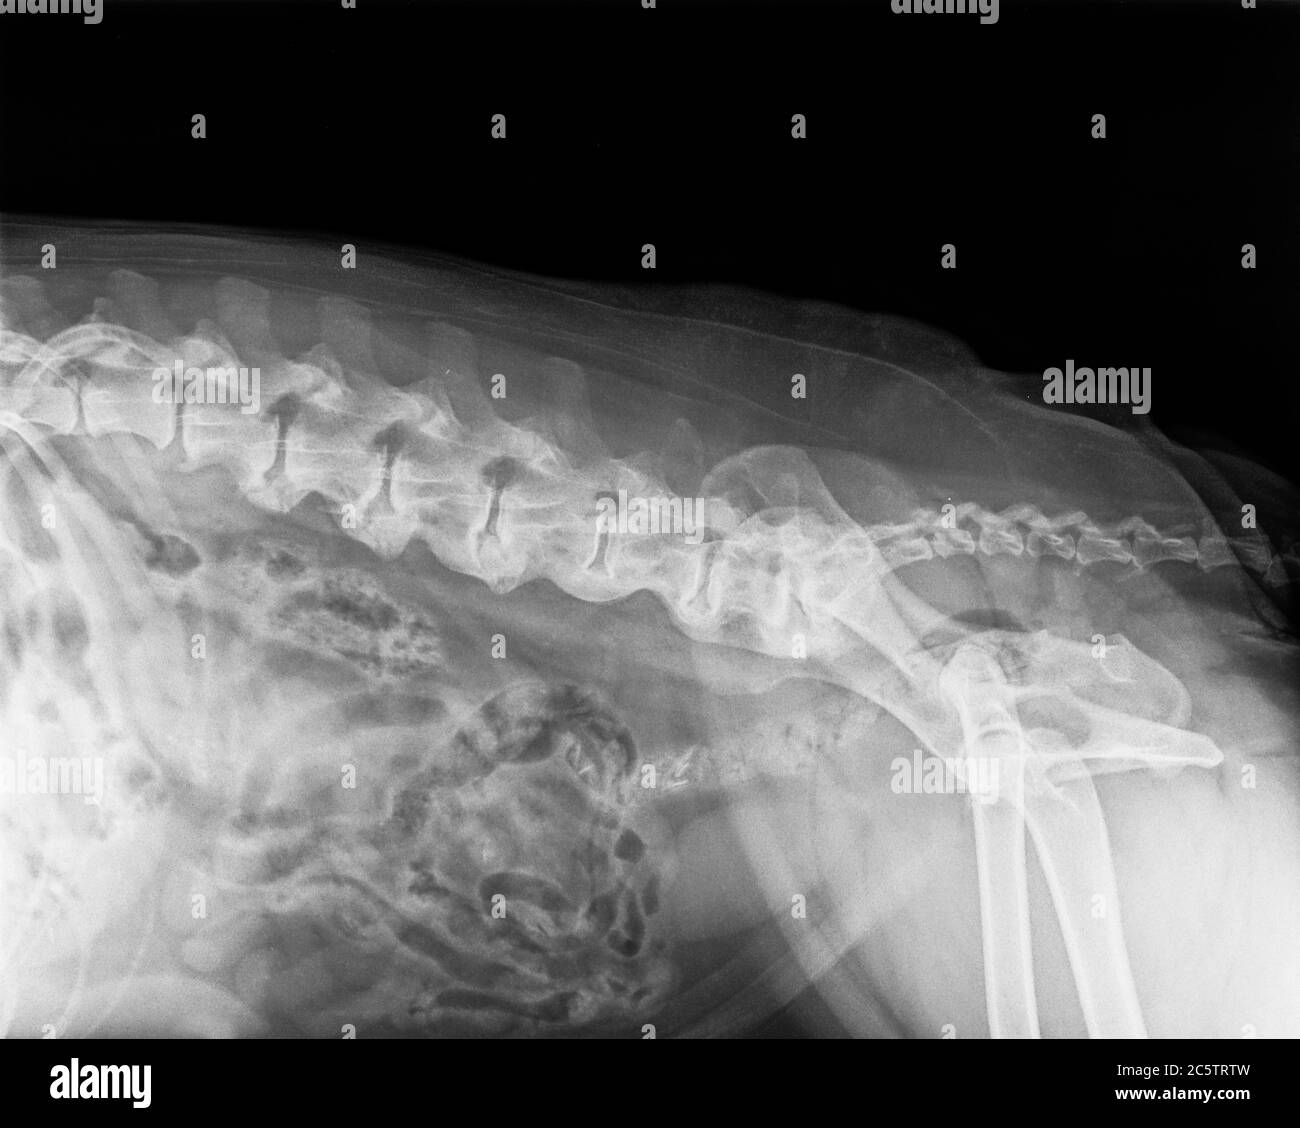

Old dog xray film present of Spondylosis deformans, a condition that Dog Bone Spurs On Spine It involves the formation of bone spurs, known as osteophytes, along the vertebrae. obvious bone spurs along spine. These bone growths are the body’s attempt to stabilise the spine in response to wear and tear, injury, or as part of the ageing. spondylosis deformans is a noninflammatory, degenerative condition of the spinal column characterized by the. at. Dog Bone Spurs On Spine.